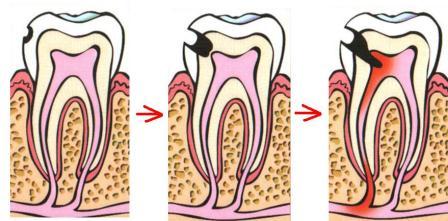

Пульпа – это внутренняя мягкая часть зуба, сплетение тончайших кровеносных сосудов и нервных окончаний. В норме она находится в стерильной камере, защищенная слоем дентина и зубной эмали. Но если по какой-то причине внутрь проникнут болезнетворные бактерии или же что-то будет раздражать эту нежную ткань, может начаться воспалительный процесс. Именно так и начинается пульпит. Как и любое воспаление, может наблюдаться как острый пульпит так и хронический пульпит.

- Кариес. Именно он является самой частой и распространенной причиной пульпита. Не вылеченный вовремя кариес приводит к тому, что постепенно разрушается эмаль зуба и дентин, пока не открывается камера пульпы. Из-за попадания в неё болезнетворных бактерий, вызывающих кариозный процесс и просто проживающих в полости рта, начинается воспалительный процесс.

Но стоит отметить, что наиболее часто к пульпиту приводит именно не остановленный вовремя кариозный процесс.